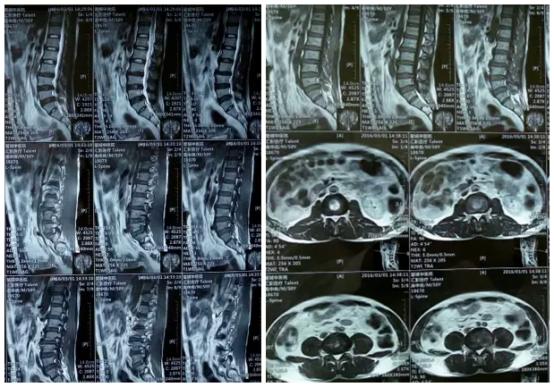

磁共振